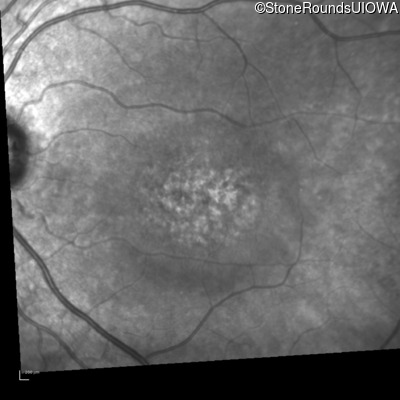

Infrared Fundus Photograph - Right - 20/200

Exemplar